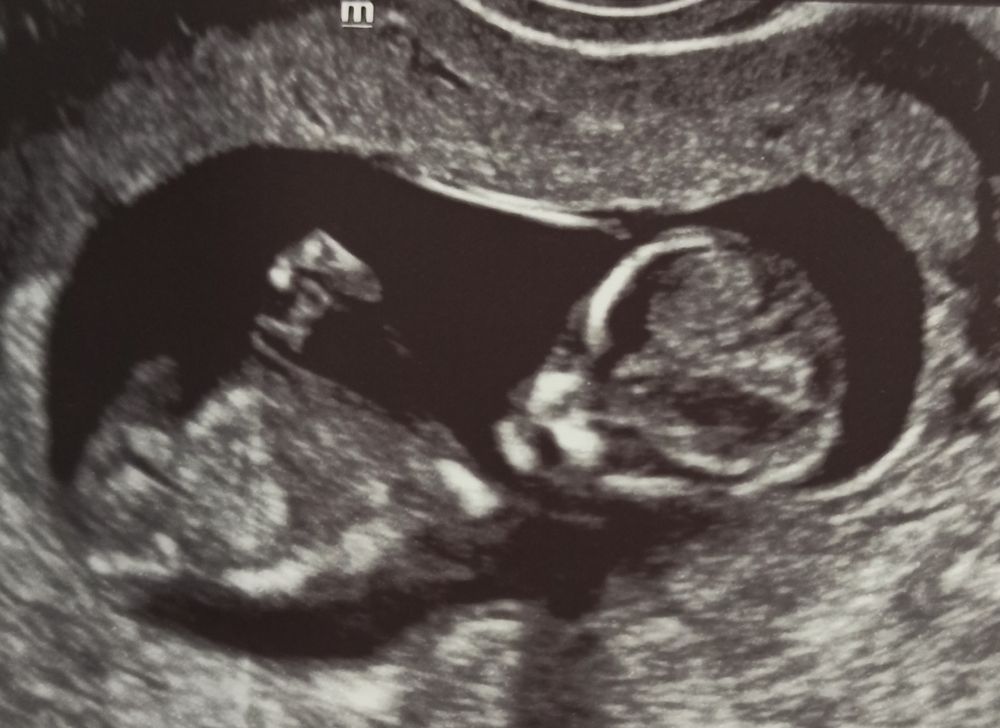

УЗИ 65 дпо (11+1) ❤🤞🤞🤞

Я стала переживать по поводу тахикардии плода, но я буду верить и надеяться, что ЧСС замедлится до нормы до 160 уд/мин, а как сейчас 170-180 уд/мин - это многовато на этом сроке (12 неделя), так частить сердечко может в норме до 9 недель, а далее должно замедляться постепенно. Домашним допплером пишет также до 170-178 уд/мин. Через неделю схожу снова на УЗИ, а потом, 2 мая будет 1 скрининг. Вот нашла табличку норм, не сильно, но превышает: